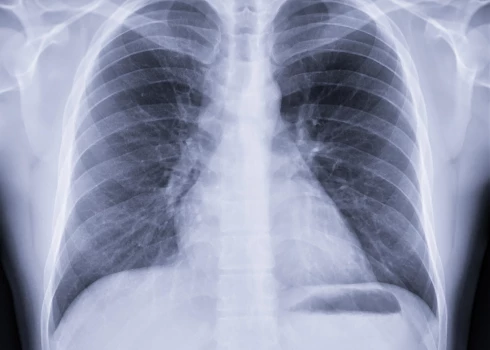

Lai gan esam beidzot sagaidījuši vasarīgus laikapstākļus, kad visapkārt viss zaļo un plaukst, diemžēl arī tam ir sava “garoziņa”. Daļai no mums ir asarojošas acis, deguna tecēšana un šķaudīšana, kas nekādi negrasās mitēties, var sagandēt arī pašas saulainākās dienas. Vēl tikai jātiek skaidrībā – saaukstēšanās vai alerģija? To mums palīdzēs izdarīt medicīnas doktors, alergologs un pneimonologs Māris Bukovskis.

Deguna gļotādas iekaisumu – iesnas – var izraisīt gan vīrusi vai baktērijas, gan alerģija. Dažādu iesnu veidu gadījumā deguna gļotādas izskats atšķiras, bet nespeciālistam ar to vien nepietiks, lai nonāktu pie konkrēta secinājuma. Taču ir arī citas atšķirības starp alerģiskajām un saaukstēšanās iesnām. Saaukstēšanās iesnas var pieņemties spēkā pakāpeniski, taču bieži vien arī strauji un akūti. Visbiežāk tās pavada arī citi simptomi, piemēram, galvassāpes vai paaugstināta temperatūra infekcijas izraisīta augšējo elpceļu iekaisuma dēļ. Deguna izdalījumu krāsa sākotnēji ir caurspīdīga, taču drīz vien to nomaina dzeltenzaļa.

Alerģiskās iesnas, sauktas arī par alerģisko rinītu, sākas strauji. To bieži mēdz pavadīt arī acu asarošana un ādas izsitumi, taču citādi pašsajūta lielākoties izteikti nepasliktinās. Deguna izdalījumi ilgstoši turpina būt caurspīdīgi. Retākos gadījumos alerģiskās iesnas var pavadīt arī elpas trūkums, tūska rīklē un aizdegunē vai klepus lēkmes. Alerģiskajām iesnām nav arī noteikts standarta ilgums – ārpus sezonalitātes – pārtraucot saskari ar alergēnu, iesnas izzūd. Spēkā, protams, ir arī pretējais – tiklīdz pacients nonāk šo alergēnu saturošā vidē, iesnas atgriežas.